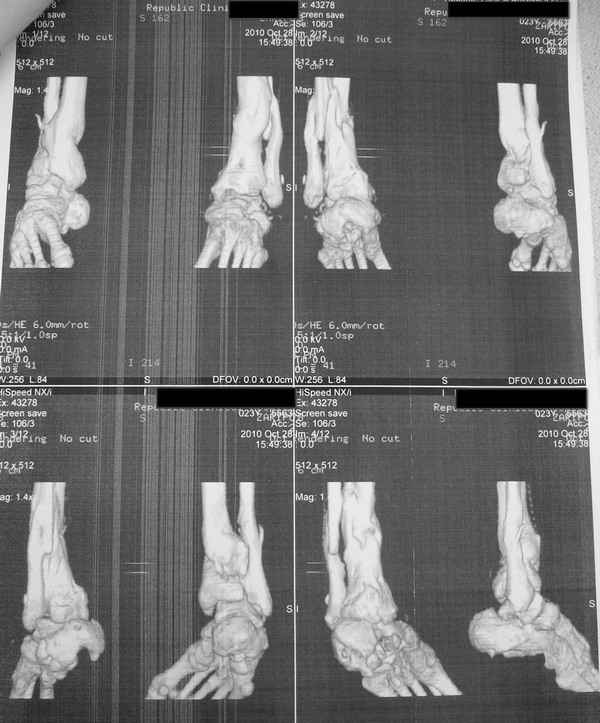

Молодая девушка со сросшимися многооскольчатыми переломами пяток и голеней.Young girl

with fractures of the calcaneus

Больная Н., 25 лет, падение с высоты (2008 г.). Жалобы на боли в области голеностопных

суставах, в области пяток при ходьбе. Лечилась в аппаратах внешней фиксации по поводу

открытых оскольчатых переломов обеих голеней, переломов пяток. Далее по поводу

несросшихся переломов голеней ЧКОС аппаратами внешней фиксации. Переломы срослись,

аппараты демонтированы весной 2010г. В левой пяточной области в месте проведения спицы

имеется сукровичное отделяемое. При ревизии гноя нет. Чем помочь девушке?

Patient N., age

25, falls from heights (2008). Complaints of pain in the ankles, in the heel when walking. She

was treated by external fixation on open comminuted fractures of both legs, fractures of the

calcaneus. Then she was treated by external fixation from nonunion of both legs. Now

fractures are fused, apparatuses removed in the spring of 2010. How to help a girl?